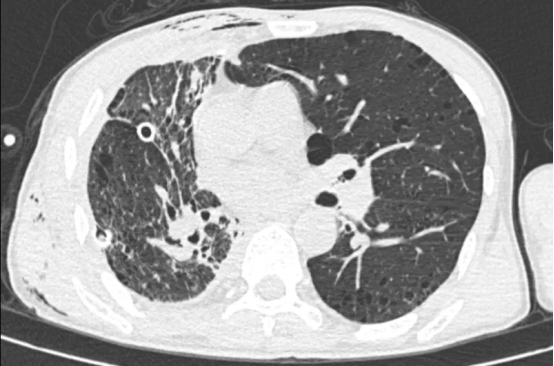

术后影像

术后,患者转入重症一科,在孙万里副主任医师的精细化治疗与护理下,患者接连闯过感染、出血、呼吸功能支持等重重难关。4天后病情趋于稳定,转回胸外二科继续康复。在医护人员的悉心照料下,患者康复出院。